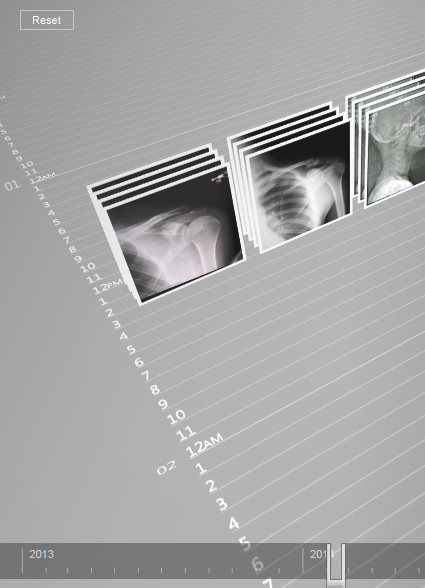

Scenario design, planning, and asset creation for future/vision videos at Microsoft. I also created demos and artifacts that could be experienced firsthand.

Digital Kitchen shot the videos, recruited cast, scouted locations, and added VFX.

︎ UX

︎ Storyboards

︎ Fake UI

︎ Engineering C#

Digital Kitchen shot the videos, recruited cast, scouted locations, and added VFX.

︎ UX

︎ Storyboards

︎ Fake UI

︎ Engineering C#